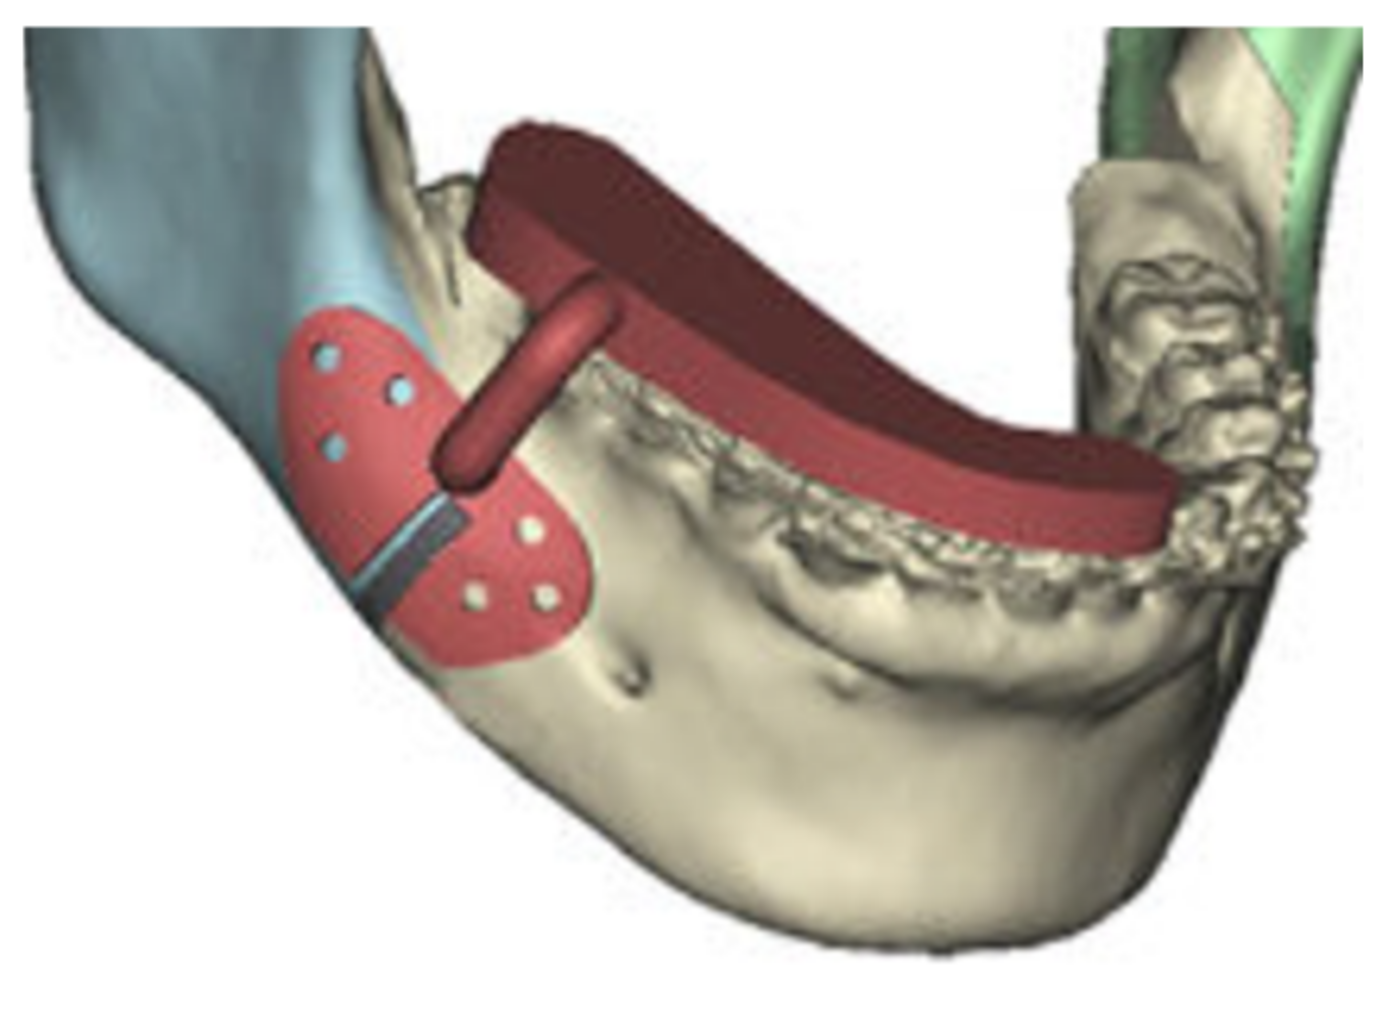

Regardless of the osteotomies’ type, the approach to design and to model the template for osteotomies is not dependent on the kind of surgery and of the final wanted results; the procedure to realize a cutting template is the same for each kind of surgery and only the final position of the osteotomized segments and the osteotomies’ path could change. In the virtual environment, the osteotomies are modelled by using solid with constant thickness (the same thickness of the drill used during the real surgery) that are subtracted (by a Boolean operation) to the CAD model of the mandible. Due to the simplicity of modelling, it is easy to define, in the virtual environment, as many models as the jaws’ configurations could be; in fact, a template that allows the cutting and repositioning of the osteotomized jaws must be able to identify and even more to fit the different configurations of the jaws: the first model for the untouched mandible, the second one for the configuration after the osteotomies’ realization, and the last one for the final position of the repositioned jaw. The telescopic effect to which the jaw is subjected after repositioning (the purple one) is shown in Figure 3.

Figure 3. Telescopic effect on the mandible.